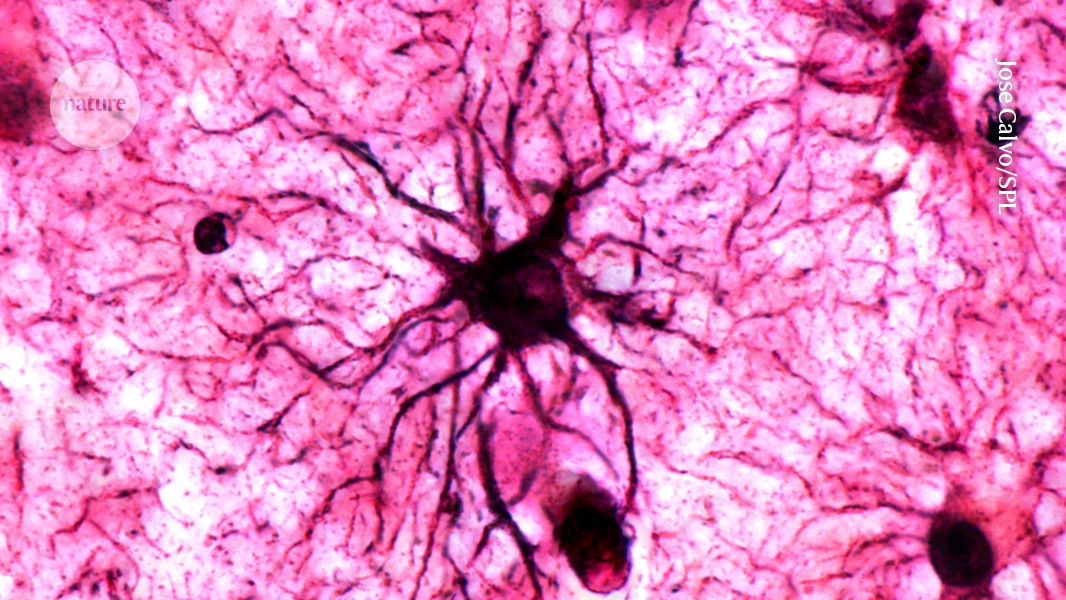

Alzheimer's Gene Network Map Reveals Hidden Brain Drivers

A team used a new machine-learning tool called SIGNET to build a cell-type-specific map of gene regulation in brains from 272 Alzheimer's patients, identifying hub genes and thousands of causal interactions—especially in excitatory neurons—offering potential drug targets while noting that causality isn’t proven and comparisons with non-AD tissue are planned.